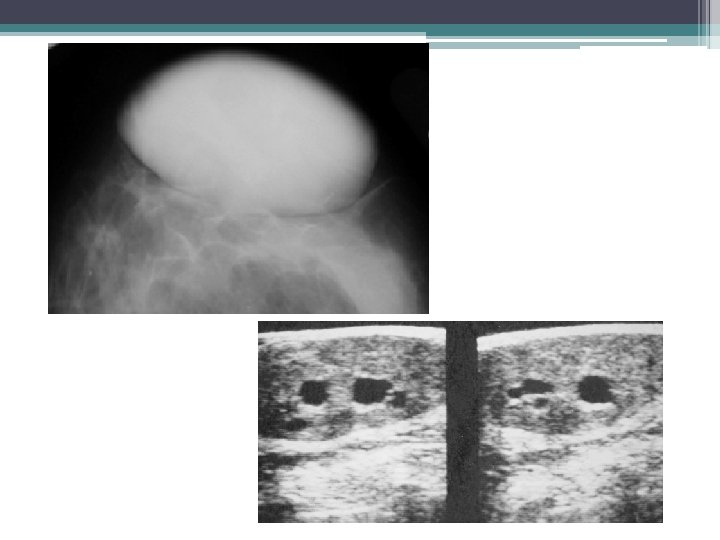

3. TUMEUR PHYLLODE • Tumeur rare, • bénigne dans 60 à 70% • souvent après 40 ans • Evolution rapide CLINIQUE • Souvent palpables : formation bien limitée, ferme, non spécifique, mais augmentant rapidement de volume.

TUMEUR PHYLLODE • MAMMOGRAPHIE: ▫ Opacité dense, arrondie, hétérogène, ▫ polylobée, bien limitée, ▫ unique et de grande taille • ECHO: ▫ Formation solide bien limitée, de contours lobulés ▫ Echostructure +/- hétérogène, pfs renforcement postérieur ▫ Remaniements kystiques ou micro kystiques: évocateur de la lésion

TUMEUR PHYLLODE • Les arguments en faveur de la malignité sont : ▫ La taille supérieure à 3 cm, ▫ La présence de microcalcifications, ▫ La présence de remaniements microkystiques. • La biopsie-exérèse large++